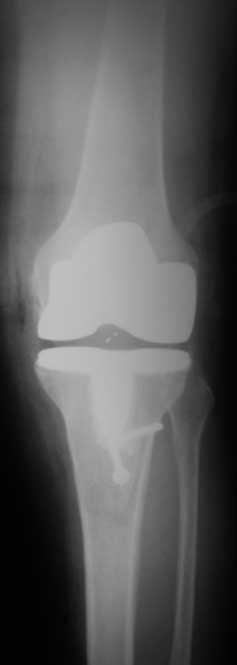

снимки

По данным R-грамм, хотя качество их не очень..., мне кажется имеется 2 основных ошибки: 1. высокий уровень остеотомии большеберцовой кости, при разгибетельных контрактурах его необходимо делать ниже.

2. Большой размер бедренного компонента. За счет этого переднезадний размер увеличен и ограничивает сгибание.